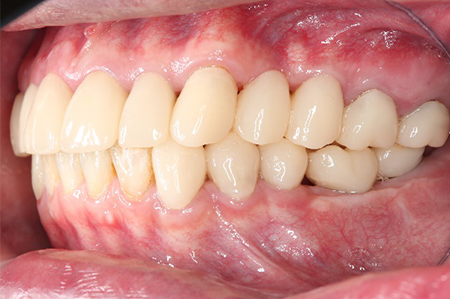

処置後、非常に審美的な補綴物が入ったことが分かるかと思います。

前歯が割れてしまってインプラントをご希望で来院された患者様です。

前歯に亀裂が入ってしまっており、抜歯後、インプラント治療を行いました。

非常に審美的な治療が出来ました。

当院では難しい前歯のインプラントも違和感なくきれいに処置することが出来ます。